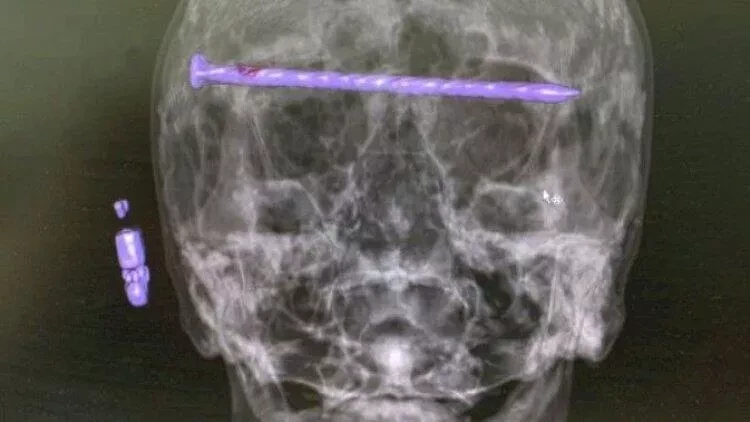

"Xəstənin kəlləsində 15 santimetr uzunluğunda bir mismar var idi. O, göz yuvalarından və gicgahdan keçirdi", - deyə həkimlər bildiriblər.

1 saylı şəhər xəstəxanasının neyrocərrahları ağır kəllə-beyin travması alan 78 yaşlı kişini əməliyyat ediblər. Məlumata görə, xəstənin həyatı xilas olunmaqla yanaşı, onun görmə qabiliyyəti qorunub.